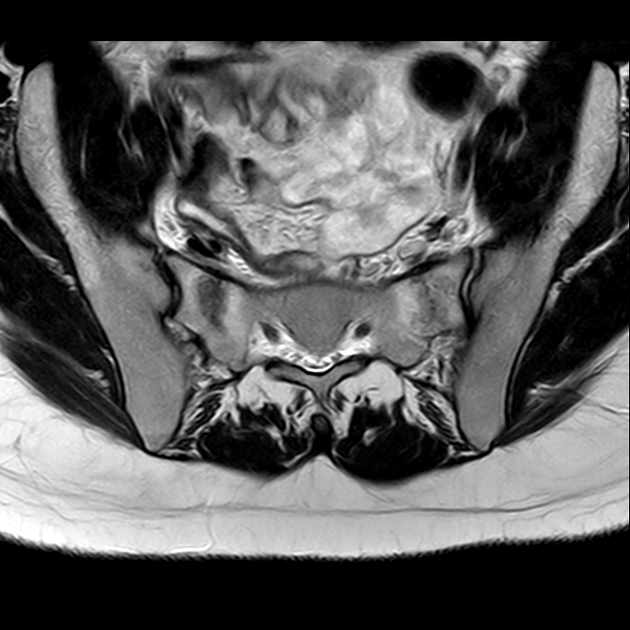

磁共振检查:

T1

T2

6、磁共振上可以发现骨折线周边明显的骨髓水肿,增强扫描明显强化

磁共振影像表现